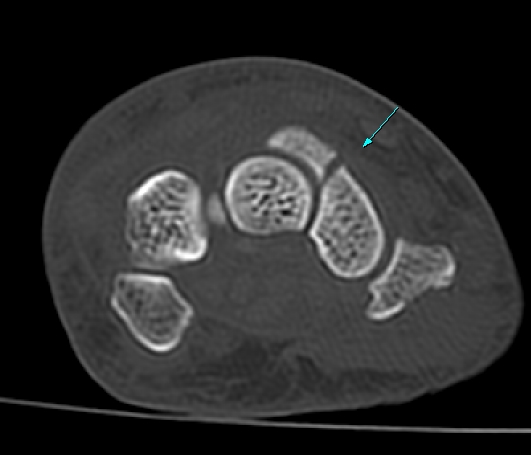

¼Õ¸ñ ÀåÃø ÁÖ»ó°ñ Á¾´Ü¸é °Ë»ç¿¡¼ ¹Ì¼¼ÇÑ ÁÖ»ó°ñ ÇÇÁú°ñ ¿¬¼Ó¼º ¼Ò½Ç(loss of cortical bone continuity)ÀÌ °üÂûµÊ(»çÁø 1, 2).